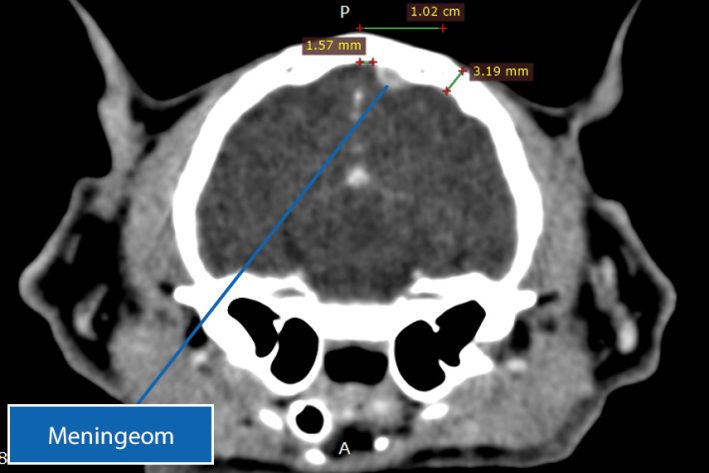

Gehirntumor (Meningeom) beim Haustier

Mittels Computertomographie lässt sich der Gehirntumor (Meningeom) genau lokalisieren und eine Operation planen.